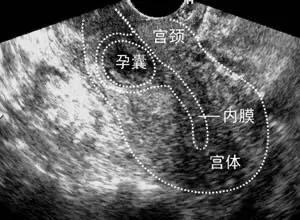

所以一旦出现这些问题,都应该引起高度重视。但有时候先兆流产也会出现这样的症状,怎么辨别呢?这就需要我们进行检查,一般我们是通过血HCG,还有超声来进行鉴别。B超有助于区别是宫内妊娠,还是宫外孕。

血HCG检测具有一定的指导意义。一般来说在宫内妊娠的血HCG能够正常的去增长,两三天之内可以翻番。如果七天血HCG都不翻番,增长不规律,就要警惕有没有宫外孕的可能,所以要结合B超看看。

此外,还有其他的一些异位妊娠,我们也可以根据病情选择手术方法。比如我们之前有一个宫角妊娠的病人,是在B超指引着下做的人流清宫术,术后继续给她用杀胚胎的药物治疗,防止刮宫不全。还有一个宫颈妊娠,这个我们是通过宫腔镜做的手术,病人恢复的也是比较好。所以我们临床上要根据病人的情况制定个体化的诊疗方案,才能达到最好的治疗效果。